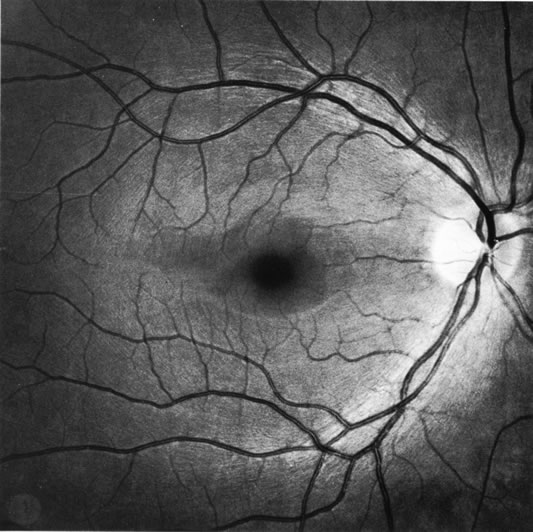

When bundles of nerve fibers drop out, their absence can be noted in the retinal sheen produced by the retinal nerve fiber layer.4,8–10,85 Such defects are easiest to see in the thickest portions of the nerve fiber layer, namely, close to the disc and especially in the arcuate bundles approaching the poles of the disc.5,6 The loss of nerve fibers can be recognized ophthalmoscopically but, as shown in Figure 41, is demonstrated most beautifully in wide-angle fundus photographs taken with blue or green filters.10,154 It is difficult to see if the background is lightly pigmented or if imperfect media produce an imperfect view of the fundus. Some observers are more skilled than others in recognizing nerve-fiber layer disease.

Fig. 41. Retinal nerve fiber layer in glaucoma. A curved wedge (between the broad arrows) represents the loss of nerve fiber bundles corresponding to a sector of the disc marked by a splinter hemorrhage (small curved arrow). (Airaksinen PJ. Mustonen E. Alanko HI: Optic disc hemorrhages precede retinal nerve fiber layer defects in ocular hypertension. Acta Ophthalmol 59:627, 1981.)